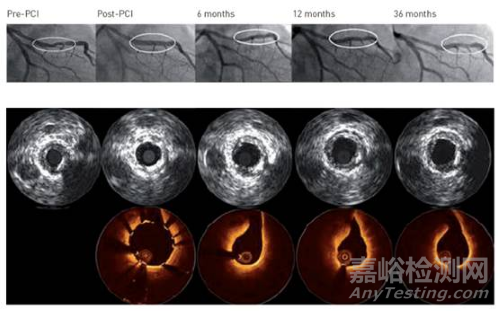

試驗(yàn)人員通過(guò)將49個(gè)DREAMS 3G和24個(gè)Magmaris支架植入48只小型豬體內(nèi)進(jìn)行降解動(dòng)力學(xué)分析。同時(shí)將另一個(gè)DREAMS 3G植入一只小型豬體內(nèi)進(jìn)行空白對(duì)照,用于730天后降解最終產(chǎn)物的結(jié)晶度分析。在第28、90、120、180和365天測(cè)定降解動(dòng)力學(xué)。

截至2023年1月,試驗(yàn)已經(jīng)完成了前三輪。通過(guò)整理90天和120天的隨訪數(shù)據(jù)得知,DREAMS 3G的不連續(xù)密度要顯著低于Magmaris支架。

而進(jìn)一步的平面分析表明,DREAMS 3G在12個(gè)月時(shí)有99.6%的骨架降解,幾乎在一年之內(nèi)完全降解,而Magmaris支架一年的鎂降解率大約為95%。兩種支架的最終降解產(chǎn)物幾乎都為磷酸鈣和少量磷酸鋁。

同時(shí),與Magmaris相比,DREAMS 3G的支架盡管更加單薄,但其不連續(xù)性明顯低于Magmaris支架,可變性更小,這也意味著DREAMS 3G能夠提供更長(zhǎng)的支撐時(shí)間。

相比于前身Magmaris 支架,DREAMS 3G在技術(shù)層面取得了更多的突破,包括采用鎂基合金材料和西羅莫司藥物涂層,在保持12個(gè)月降解時(shí)間的同時(shí),也兼顧了徑向支撐耐久能力。

BIOMAG-I試驗(yàn)數(shù)據(jù)顯示,DREAMS 3G在安全性方面繼承了前代的優(yōu)點(diǎn),試驗(yàn)過(guò)程中靶病變失敗率較低,同時(shí)基本沒(méi)有支架血栓形成病例。

此外,血管造影顯示支架內(nèi)晚期管腔損失(LLL)得到了明顯改善。平均LLL為0.21 mm,中值為0.13 mm。而目前新一代永久性鈷鉻藥物洗脫支架DES2的LLL中值為0.18 mm左右,DREAMS 3G的優(yōu)勢(shì)較為明顯。